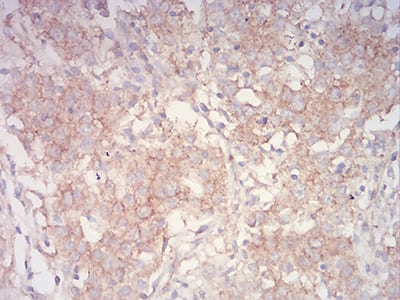

- Immunohistochemical analysis of paraffin-embedded human stomach cancer tissues using PYCARD mouse mAb with DAB staining.